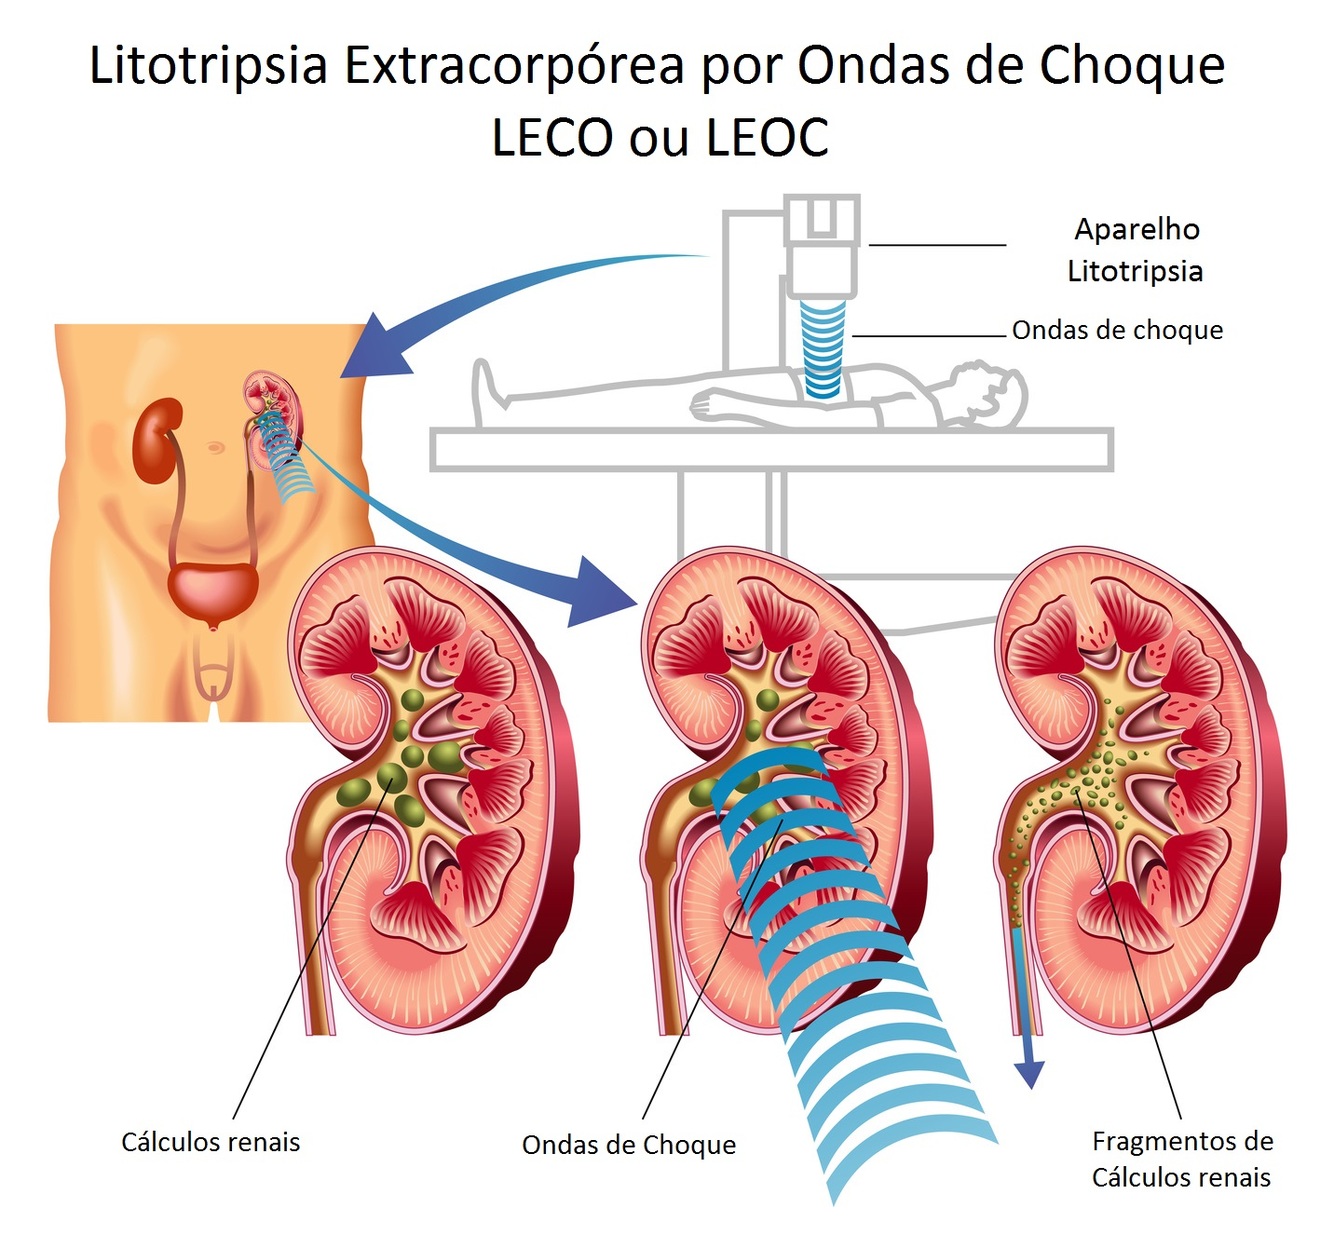

- Litotripsia Extracorpórea (LECO)

Qual a indicação de Litotripsia Extracorpórea na Nefrolitíase Aguda?

Cálculo proximal e < 2 cm

Quais as principais contraindicações à Litotripsia Extracorpórea?

- Gestação

- Aneurisma de Aorta Abdominal